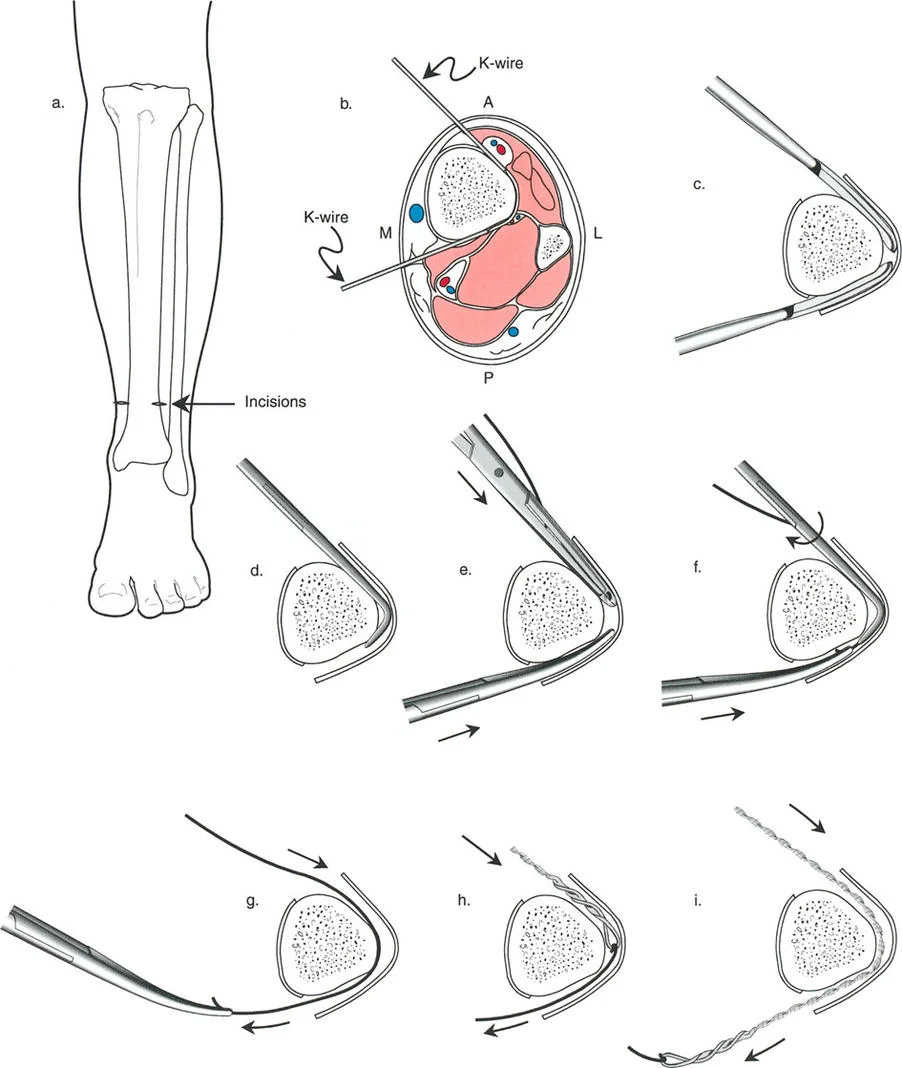

قيود الأسلاك والدبابيس في القاعدة 2

لتحقيق هذه الترجمة الضرورية والمقصودة بسلاسة باستخدام إطار دائري كامل الأسلاك، يلزم استخدام أسلاك الزيتون المعاكسة (counter-opposed olive wires). تعمل أسلاك الزيتون كقوى سحب ديناميكية، تسحب قطعة العظم على طول الحلقة أثناء فتح المفصلات. بدون أسلاك الزيتون، سيبقى العظم ثابتًا بينما تتحرك الحلقة عبر الأنسجة الرخوة، مما يسبب نخرًا شديدًا في الجلد.

على العكس من ذلك، إذا تم استخدام دبابيس نصفية (مسامير شانز)، فإنها تقيد العظم بطبيعتها بالحلقة. نظرًا لأن الدبابيس النصفية هي أذرع صلبة (مثبتة من طرف واحد بالحلقة ومغروسة في العظم من الطرف الآخر)، فإنها لا تسمح للعظم بالانزلاق على طول محور السلك. هذا يجعل أسلاك الزيتون غير ضرورية للترجمة في منشآت الدبابيس النصفية، ولكنه يتطلب من الجراح التأكد من أن الدبابيس النصفية قوية بما يكفي (عادةً دبابيس بقطر 5 مم أو 6 مم مطلية بهيدروكسي أباتيت) لتحمل لحظات الانحناء الناتجة عن الترجمة.